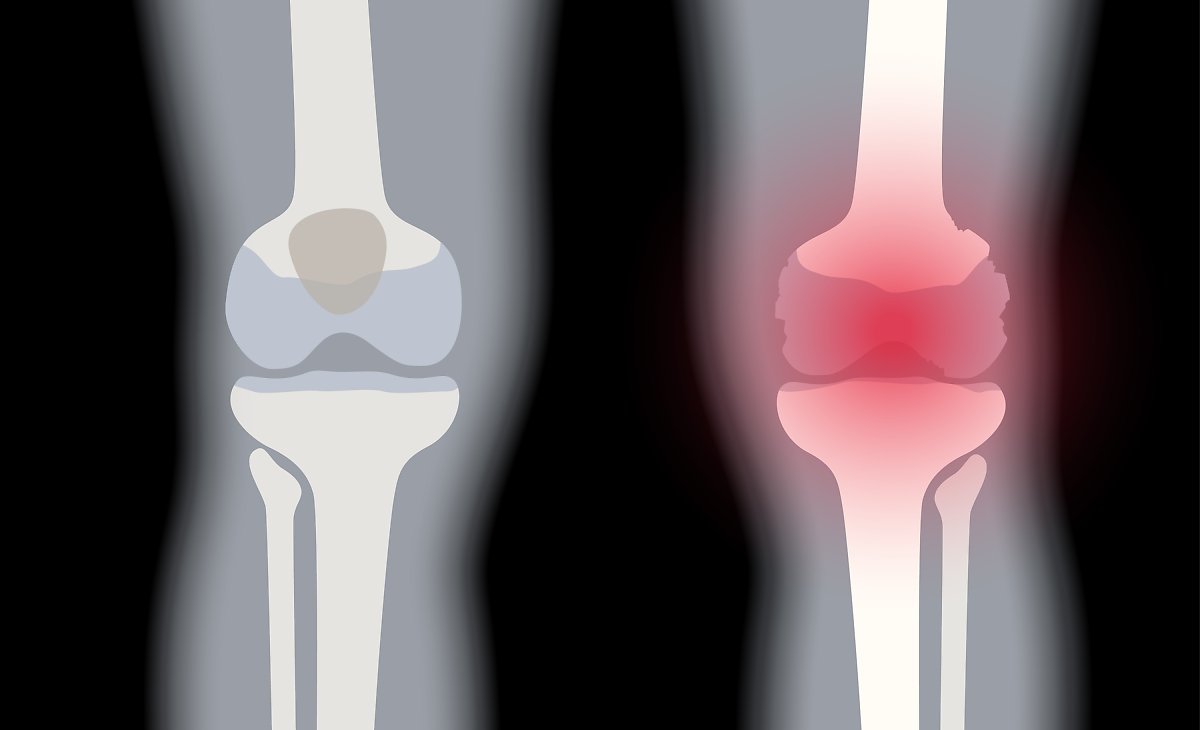

3. 고관절 통증 증상 - 퇴행성 고관절염

연골이 닳으면서 관절 사이 간격이 줄어들고 통증과 강직이 나타납니다. 초기에는 소염진통제나 연골 보호제, 휴식과 적절한 운동으로 경과를 관찰하며 보존적 치료를 시도합니다. 보존적 치료로 증상이 호전되지 않거나 기능 저하가 심하면 수술적 치료를 고려할 수 있습니다.

5. 퇴행성 관절염

연골 보호층이 닳아 없어지면 뼈와 인대에 손상이 발생하고 염증과 만성 통증이 생깁니다. 연골 손상으로 인한 통증은 회복이 더디므로 조기 관리가 필요합니다.